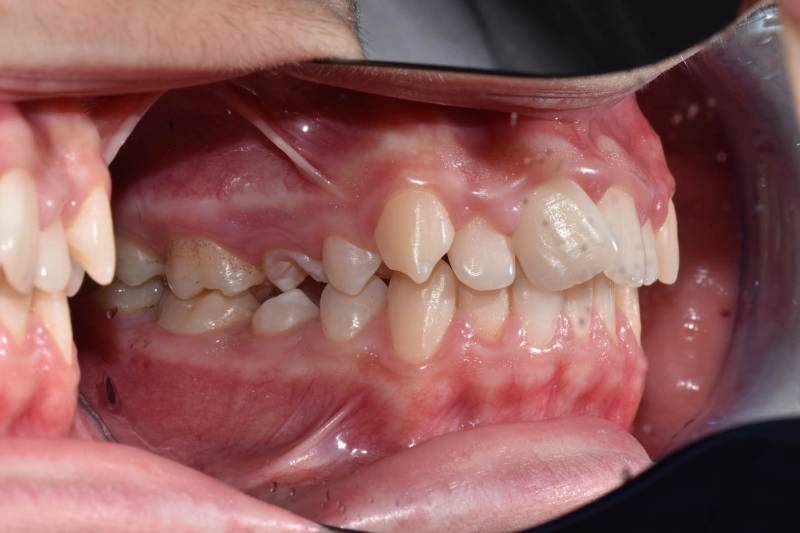

Paziente trattato con ortodonzia tradizionale fissa bimascellare per 20 mesi.